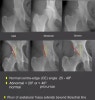

Hip dysplasia

Centre-edge(CE) Angle

Acetabular index

Proximal femur morphology

- Cartilage and joints

① 어린이에 있어서는 눈물방울과 대퇴골두 사이의 관절 공간이 넓어져 있고 관절의 삼출물이 보일 수 있습니다.

② 양측 관절의 차이가 2mm 이상의 경우 임상적으로 중요합니다.